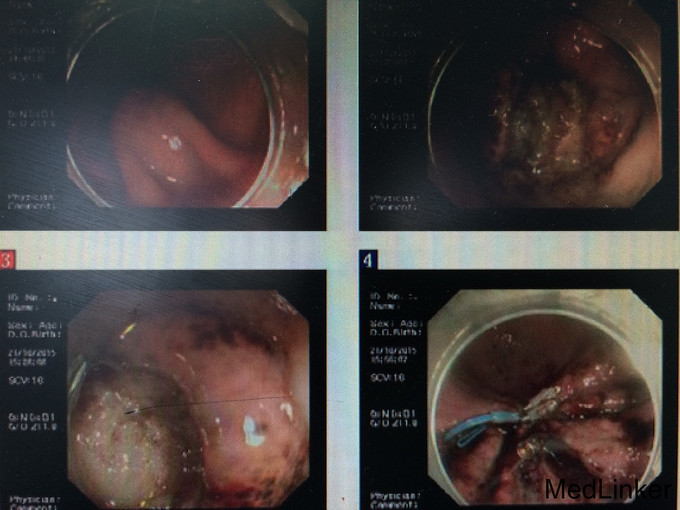

患者,女,59岁 主诉:发现胃粘膜下肿瘤2年余 现病史:患者于2013-09-24日因胃底高级别上皮内瘤变、食管乳头状瘤、胃底粘膜下肿瘤在我院行ESD。术后恢复好。于2013-10-17复查超声内镜示:胃底粘膜下低回声占位(间质瘤可能大),于2013-12-13日复查胃镜示胃粘膜下肿瘤。2014-01-02于我院行ESD,手术过程出现血压波动较大,遂停止操作。2014-10-17日再次于我科拟行胃ESD术中因血压波动大中断手术。2015-09-19我院门诊复查内镜示:胃ESD术后,胃粘膜下隆起,糜烂性胃炎。活检:(胃窦)送检粘膜组织表面糜烂慢性炎,少量腺上皮低级别内瘤变,间质充血,散在炎细胞浸润,HP(+)。2015-09-19日于外院查上腹部增强CT示:胃底部间质瘤。 既往史:“高血压病”病史20余年,最高180/100mmHg,自服缬沙坦、倍他乐克降压治疗,平素血压控制可;糖尿病史15年,自服格列美脲片、二甲双胍降糖治疗,自诉血糖控制良好。17岁时因卵巢囊肿行囊肿切除术,2013-09-24在我院行ESD术,“青霉素”过敏史。

专科检查:无特殊。 辅助检查:2015-09-19我院门诊复查内镜示:胃ESD术后,胃粘膜下隆起,糜烂性胃炎。活检:(胃窦)送检粘膜组织表面糜烂慢性炎,少量腺上皮低级别内瘤变,间质充血,散在炎细胞浸润,HP(+)。2015-09-19日于外院查上腹部增强CT示:胃底部间质瘤。

住院期间主要检查结果:心脏彩超示:左室肌顺应性下降。超声内镜示:胃底粘膜下隆起(间质瘤可能大),糜烂性胃炎。余未见特殊异常。 诊疗经过:完善入院常规检查,排除禁忌,于2015-10-21日拟行ESD,在切除过程中发现瘤体部分位于腹腔内,遂停止切除,用止血钳夹闭创面。术后予禁食、抑酸、止血、消炎及补液支持治疗。